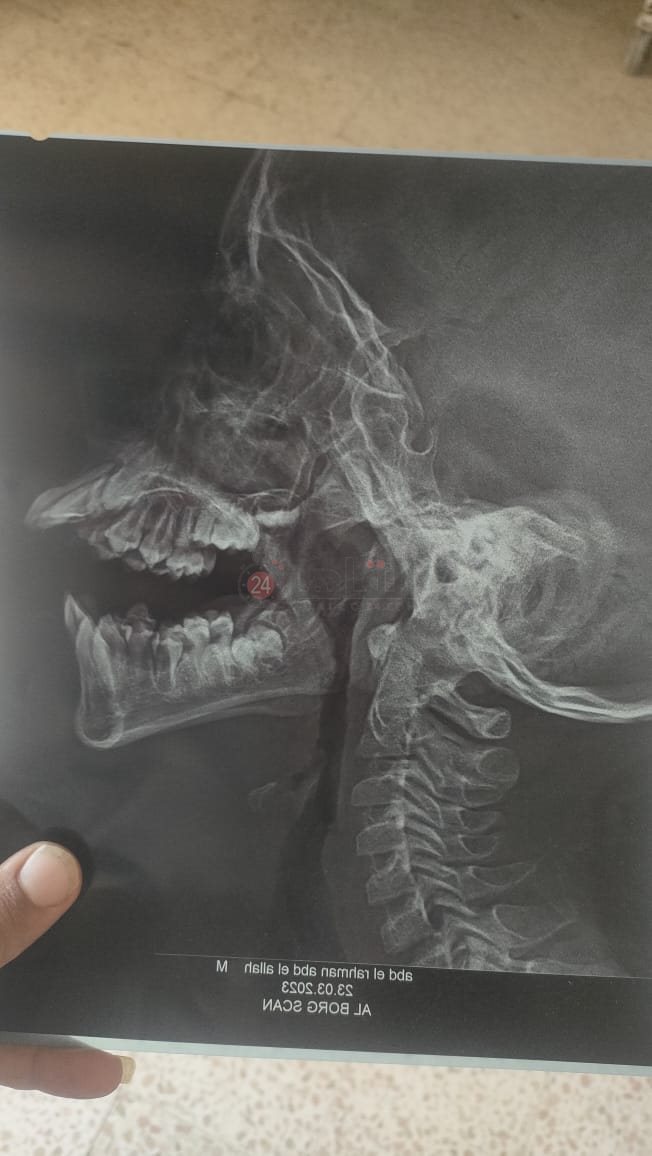

أقدم مُسن بمنتصف العقد السابع من العمر على الإضراب عن الطعام منذ 6 أيام وحتى الآن؛ بعدما ضاق ذرعًا بأزمة بيئية تُهدد حياته وحياة أبنائه وأحفاده جراء وجود غربال مُخصص لإزالة الأتربة من لب عباد الشمس وسط كتلة سكنية في إحدى العزب التابعة لنطاق ودائرة مركز أولاد صقر في محافظة الشرقية، والذي تسبب في إصابة الرجل واثنتين من زوجات أبنائه وثلاثة من أحفاده بـ تضخم في غضاريف الأنف والتهاب بالجيوب الأنفية وحساسيه على الصدر.